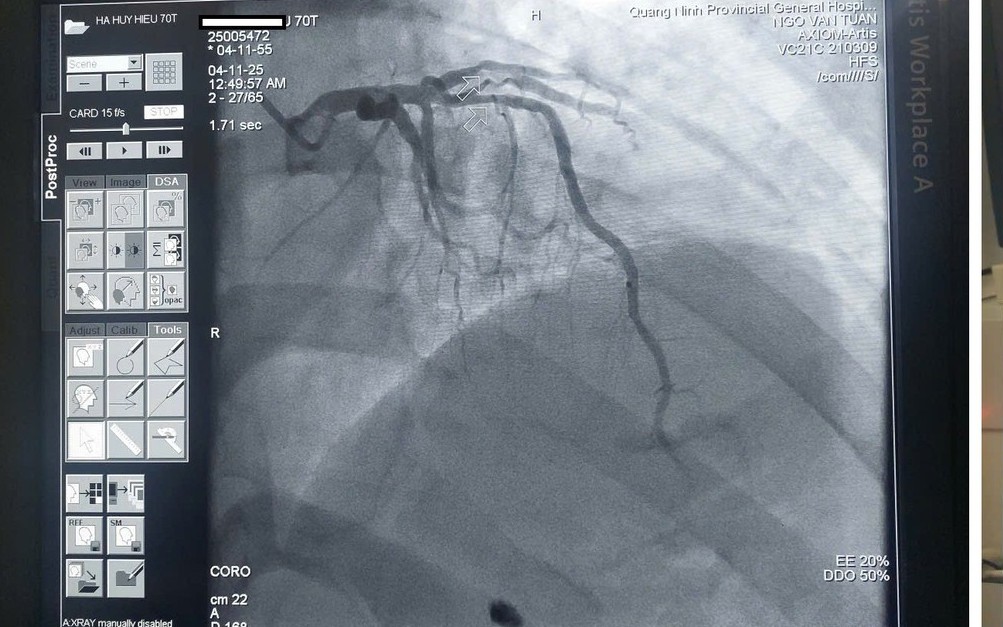

Kết quả chụp mạch vành cho thấy bệnh nhân bị tắc mạch ngay vị trí xuất phát của động mạch liên thất trước – đây là một trong hai động mạch chính cung cấp máu nuôi tim. Qua hội chẩn, các bác sĩ xác định bệnh nhân bị nhồi máu cơ tim cấp và nhanh chóng tiến hành can thiệp nong bóng, đặt stent tái thông mạch vành. Nhờ được cấp cứu kịp thời trong "thời gian vàng", bệnh nhân đã qua cơn nguy kịch và hiện sức khỏe ổn định.